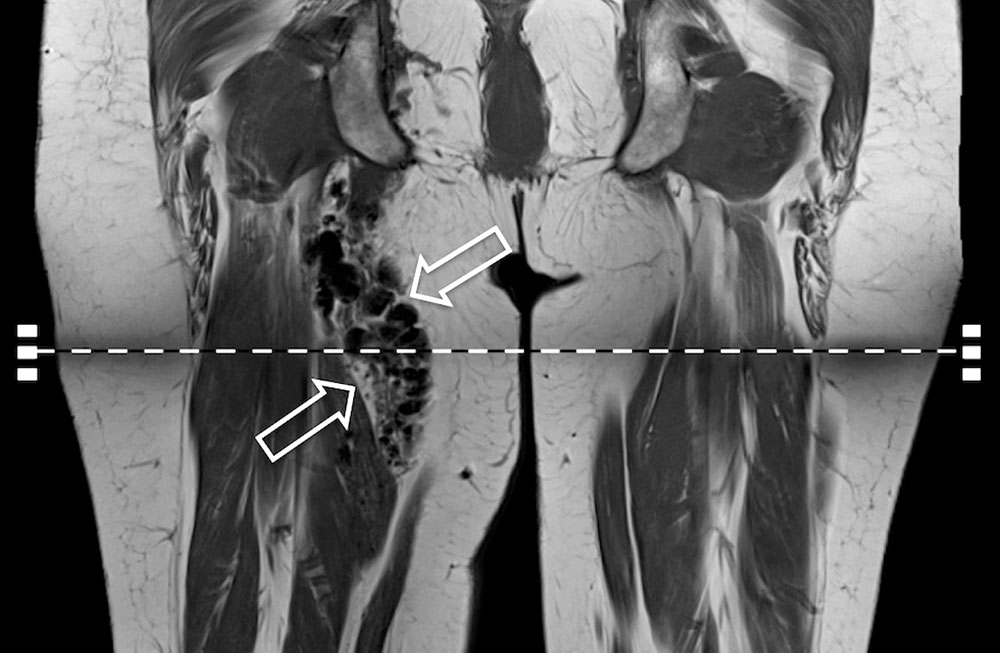

The imaging appearance is characterized by a large number of dilated inflow and outflow vessels, which extend into the surrounding tissue layers, usually without respecting classic anatomical borders. Imaging does not show an actual solid, circumscribed tissue lesion in the sense of a space-occupying mass, as often seen in vascular tumors. Rather, the absence of a defined solid mass is an imaging characteristic of an arteriovenous malformation (AVM). The nidus, as a net-like tangle of multiple small arteries and veins, presents as a localized proliferation of multiple, smaller vessels (“bag of worms”). Displacement of soft tissue that is characteristic of solid tumors is normally absent.

In addition, cross-sectional imaging using computed tomography (CT) or magnetic resonance imaging (MRI) is required to confirm the diagnosis, localization and involvement of organs. CT with contrast agent administration plays a lesser role in this context: it can easily detect bony involvement of the arteriovenous malformation, but spread to soft tissues is better visualized by MRI. The hemodynamics of the lesion can also be visualized by dynamic, contrast-enhanced MR angiography. In MRI, so-called flow voids are present in sequences without contrast medium because of the rapid blood flow. The dilated arteries supplying the nidus ("feeder arteries") usually follow a tortuous course. Depending on the angioarchitecture, single dominant dilated veins or several more net-like dilated veins can be delineated as the outflow of the lesion. The surrounding tissue may show edematous or fibrous-fatty changes. Involved bony structures may exhibit lytic changes or hyperplasia.